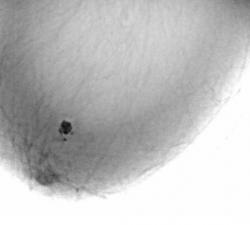

Протокол исследования. Общий фон инволютивно измененной молочной железы (в годы климакса). В правой молочной железе в передних отделах, в верхнем наружном квадранте определяется «узловое образование» значительной интенсивности, однородной структуры (1), неправильно округлой формы, с неровными, местами волнистыми контурами. В окружающей ткани определяются несколько различных размеров очаговых теней значительной плотности. Описанные тени располагаются на фоне локального снижения прозрачности молочной железы (стрелки) – по всей видимости - участок нежного склероза (1 – прямая проекция, 2 – боковая проекция). 3, 4, 5 – патологический участок железы выделен «навигатором», проведена цифровая обработка изображения – тень неоднородной структуры с преимущественным обызвествлением по периферии и известковыми включениями в центре.

Заключение: Инволютивная молочная железы в годы климакса. Фиброаденома (обызвествленная) правой молочной железы с более мелкими обызвествленными фиброаденомами вокруг.